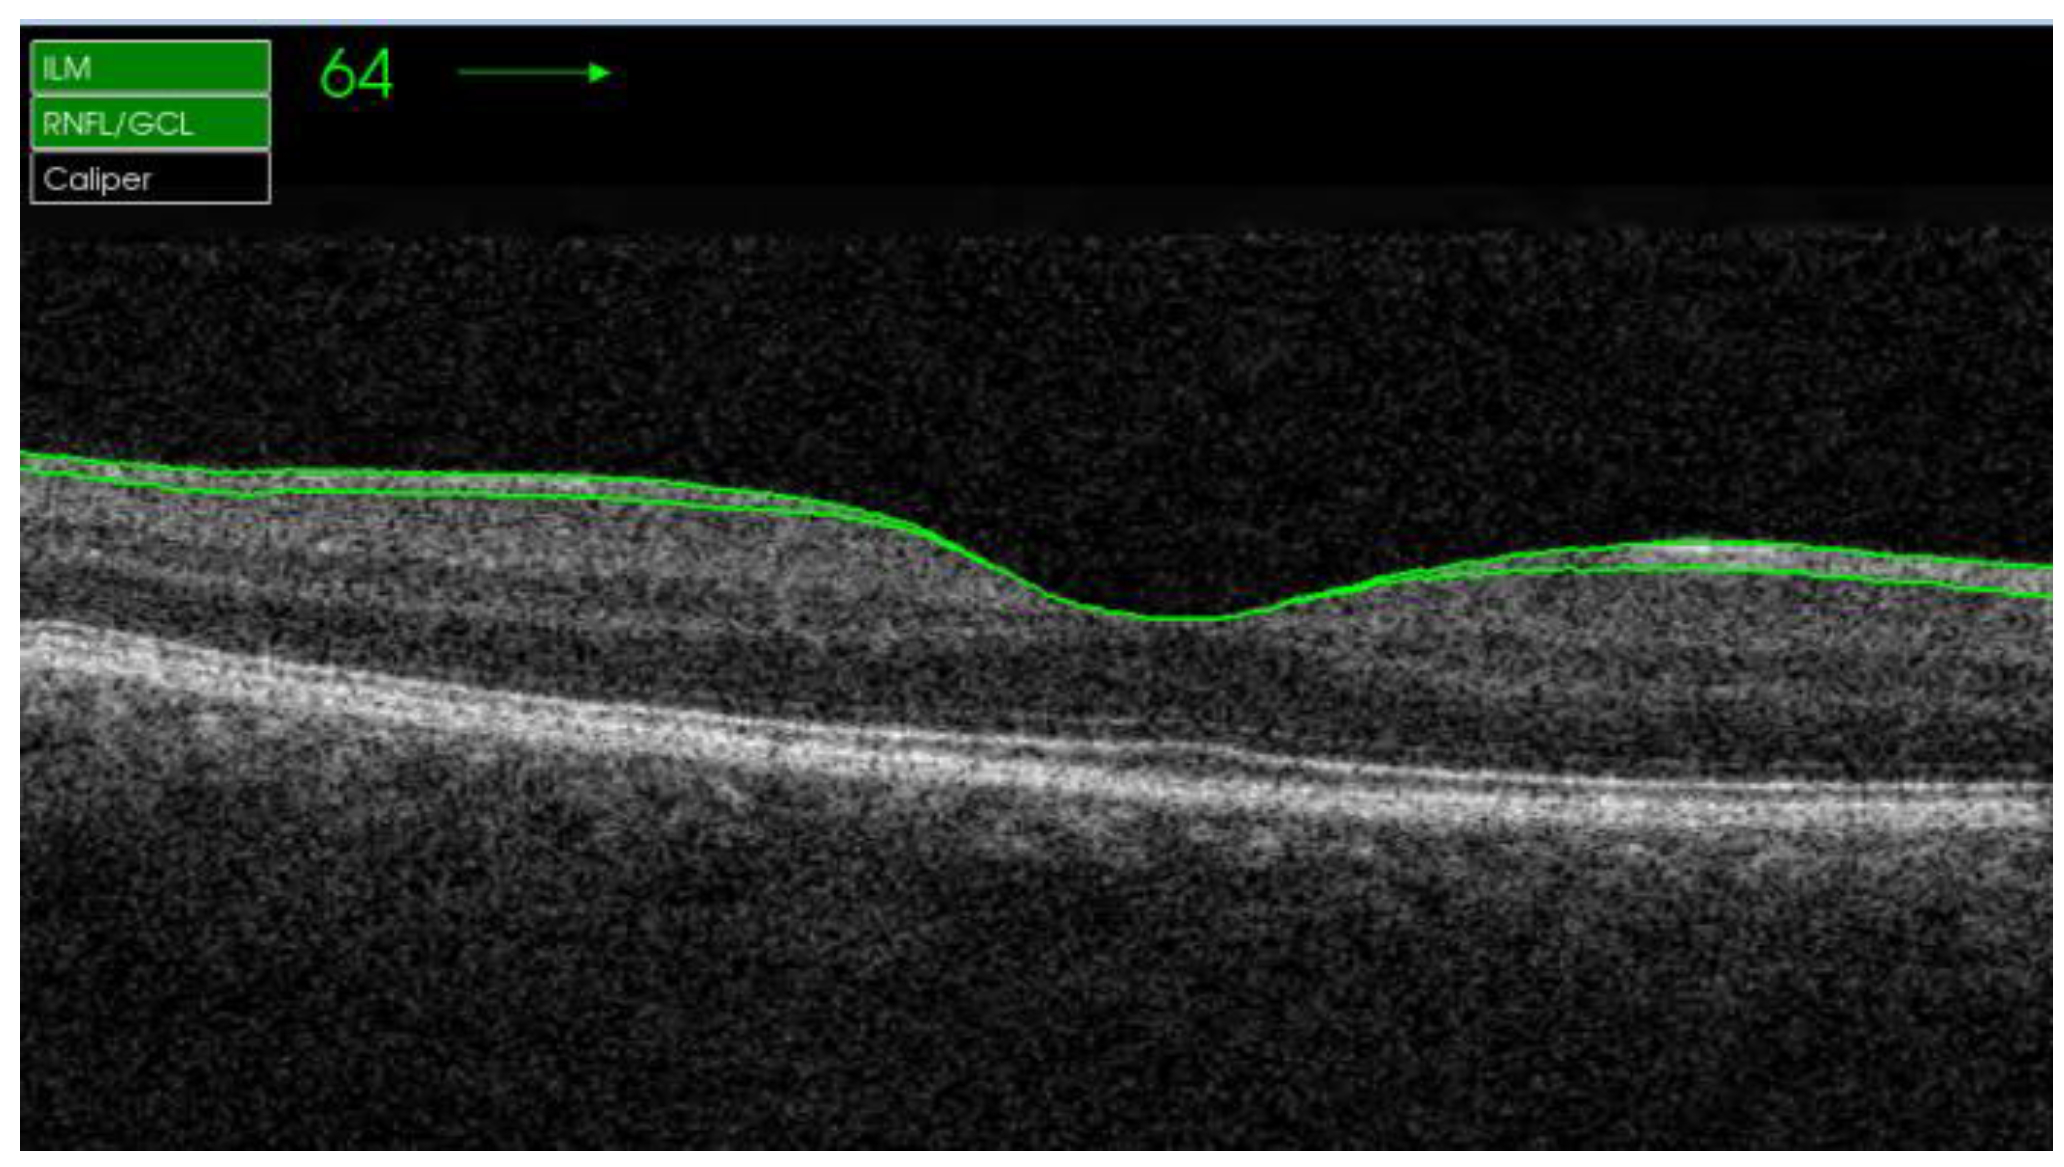

2.2. Procedures